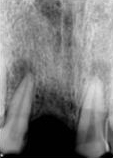

antes depois